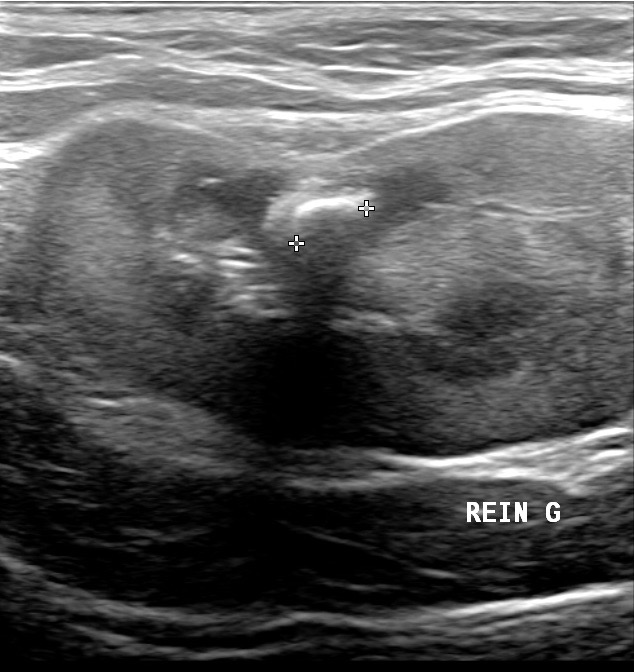

Deux images d’ascite importante chez des chats atteints de PIF : à gauche, seule la mince paroi de la vessie permet de distinguer le liquide à l’intérieur (l’urine) du liquide à l’extérieur (l’ascite). A droite : un rein perdu au milieu du liquide d’ascite ; on remarquera au passage la corticale rénale hyperéchogène, et aussi la présence d’un anneau médullaire (ou « medullary rim », cette ligne hyperéchogène qui suit la jonction cortico-médullaire) marqué : dans une étude portant sur la signification de cette image échographique dans le rein des chats (Ferreira & Coll, 2020), sur 23 chats atteints de PIF, 15 présentaient cet anneau médullaire, le plus souvent épais, et 8 ne le présentaient pas. Pour les auteurs, cette différence permet de conclure à une association significative entre anneau médullaire et PIF. Donc un indice diagnostique intéressant mais bon, ce n’est pas parce qu’on voit un anneau médullaire dans le rein d’un chat que celui-ci a forcément la PIF, et réciproquement !